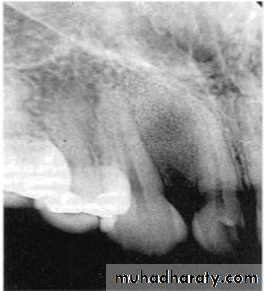

• B: Ill Defined Borders:

Blending border into adjacent area –gradual transition-normalappearing bone & abnormal appearing trabeculae -sclerosing osteitis• Invasive irregular border-bone destruction-malignancy.

Invasive irregular border-bone destruction/SCC